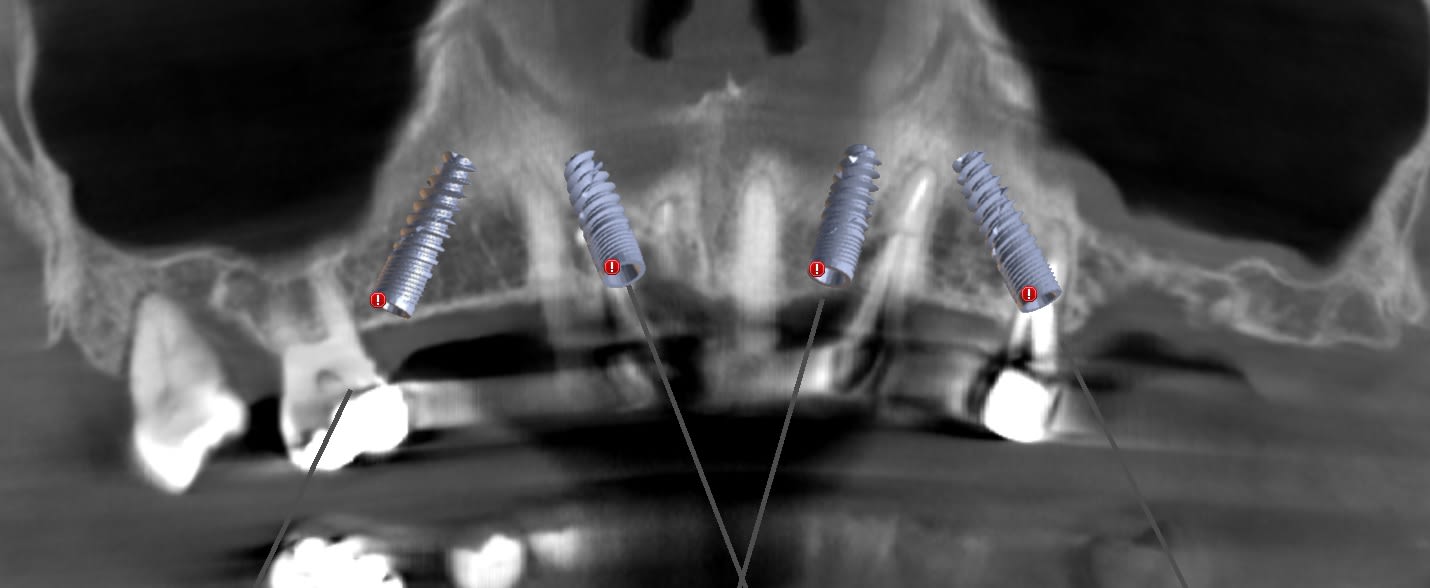

cas 3 : patient 50 ans. avoir des 7 est plus important . implants plus court : 4 de 12, un 14 et un 10. émergence des implant en 14 24 : obligation de chercher un appuis postérieur : deux ptérygoidiens.

Pas de guide à étage : guide appuis osseux, bridge a armature métal avec pilier collé en bouche avec indexation du bridge grâce aux clavettes du guide.